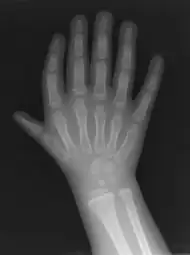

Triphalangeal thumb (TPT) is a congenital malformation where the thumb has three phalanges instead of two. The extra phalangeal bone can vary in size from that of a small pebble to a size comparable to the phalanges in non-thumb digits. The true incidence of the condition is unknown, but is estimated at 1:25,000 live births.[1] In about two-thirds of the patients with triphalangeal thumbs, there is a hereditary component.[2] Besides the three phalanges, there can also be other malformations. It was first described by Columbi in 1559.[3]

The diagnosis can be made on a physical examination and on an X-ray.[4]

Classifications

There are multiple classifications for the triphalangeal thumb. The reason for these different classifications is the heterogeneity in appearance of the TPT. The classification according to Wood [10] describes the shape of the extra phalanx: delta (Fig. 4), rectangular or full phalanx (Table 1). With the classification made by Buck-Gramcko a surgical treatment can be chosen (Table 1). Buck-Gramcko differentiates between six different shapes of the extra phalanx and associated malformations.[11]